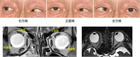

1. 複視とは、見ている物体(対象物)が二つ以上に見える(ダブる)ことで、単眼複視と両眼複視がある。

1. 両眼複視には、左右にダブる水平複視、上下にダブる上下複視、傾いてダブって見える回旋複視の3つがある。